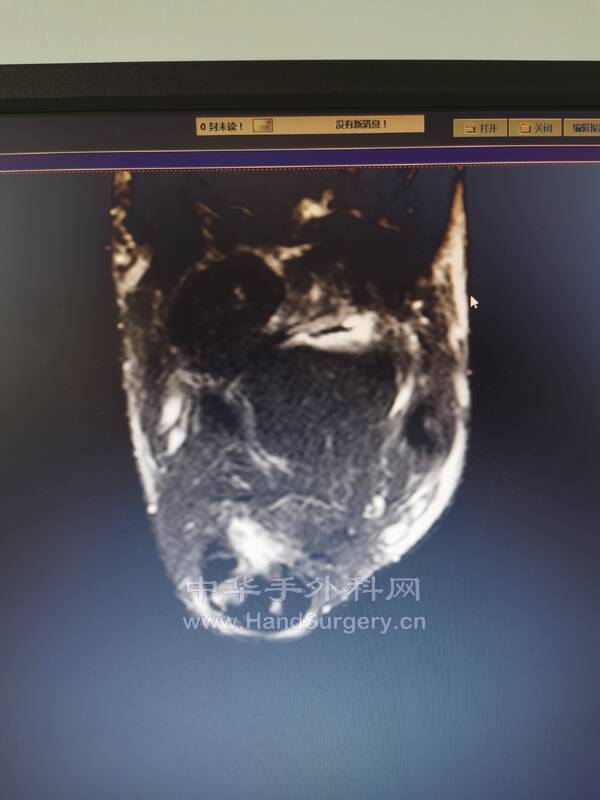

比如这个患者

跟腱止点断裂

再看核磁影像,手术所见历历在目